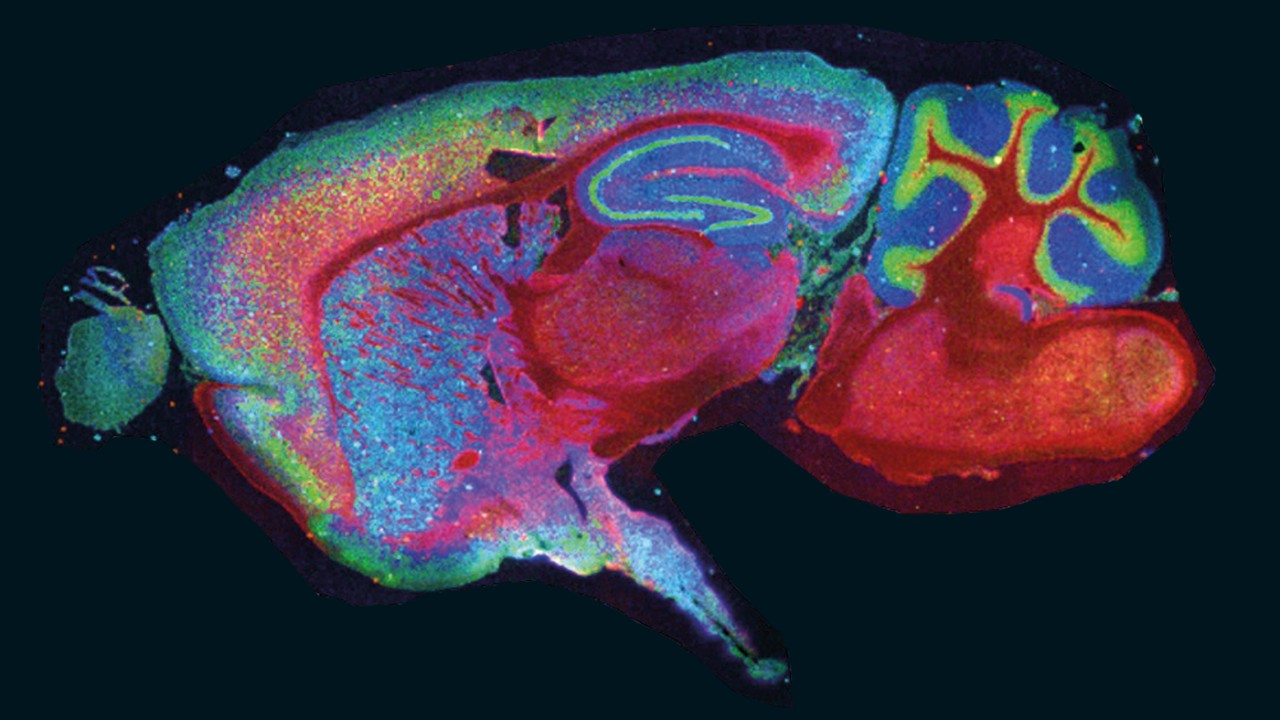

Four proteins distributed in rat brain. Two insets show protein ion Images overlaid with histology image. Note the strong localization to sub-structures.